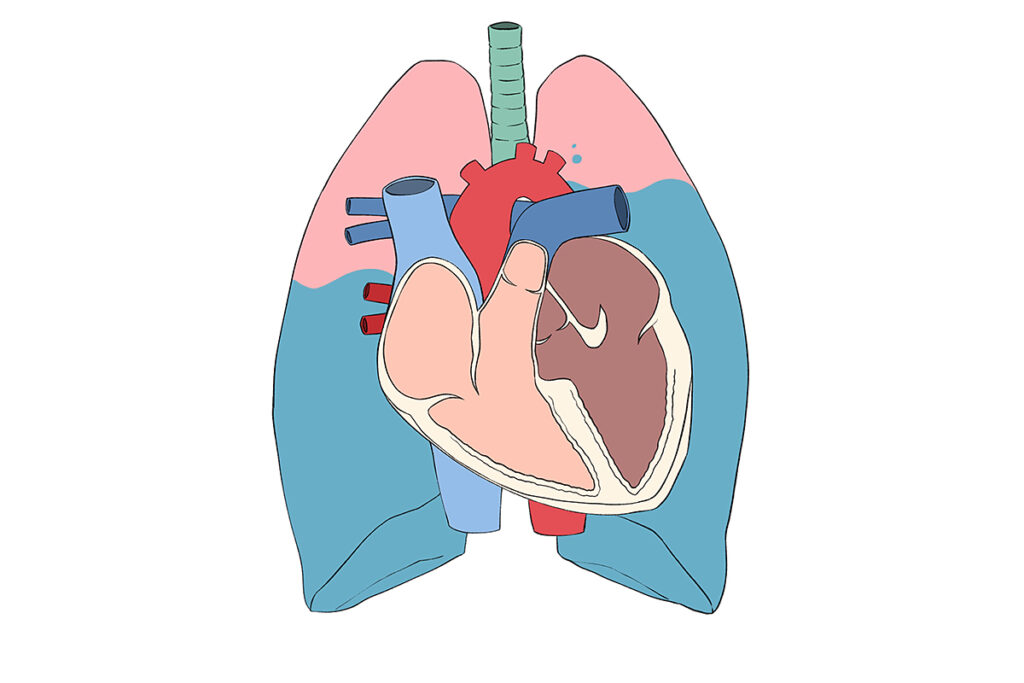

さらに悪化すると、肺⽔腫(肺に⽔が溜まる状態)を起こし、陸にいながら溺れているよ

うな⾮常に苦しい状態になることもあります。